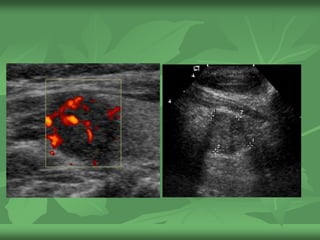

 Explanation: Color Doppler

image of the same nodule

demonstrates mainly

peripheral, and little internal

vascularity. Peripheral

vascularity is not suspicious.

In this otherwise borderline

nodule, the predominant

peripheral vascularity

strengthens the

recommendation against

FNA.

 Pathology: Follicular lesion

Nodule measures 1.8 cm in greatest

dimension

Recommendation: No FNA

Explanation: The

composition is mixed cystic-

solid. There are no

calcifications. Since it is < 2

cm, FNA is not

recommended. 1.8 cm is

borderline in size for a

mixed cystic-solid nodule

and vascularity could help

in this case.

Mismo caso

Recommendation:

FNAExplanation: Color

Doppler image of the same

nodule demonstrates

predominantly internal

vascularity. Internal

vascularity is suspicious. In

this otherwise borderline

intenal vascularity leads to

the recommendation for

Pathology: Papillary

carcinoma